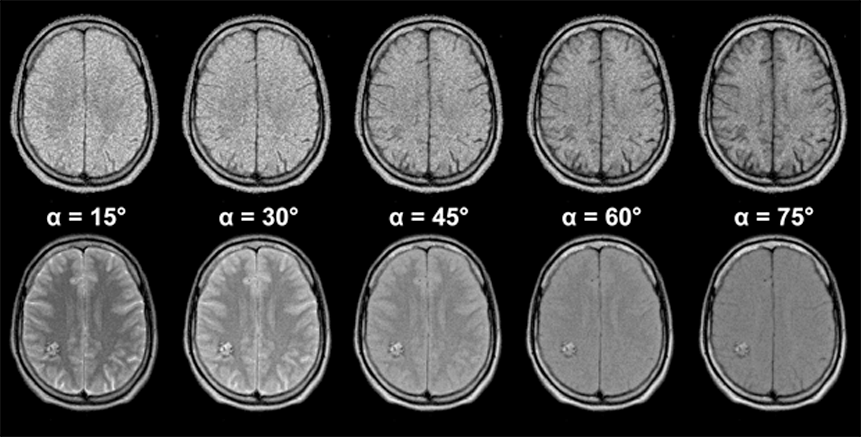

Figures 10-12 and 10-13 depict the typical signal intensity behavior of a GRE se­quen­ce, in this case a spoiled FLASH sequence. Commonly, the signal in­­ten­­si­­ties reach a maximum between 30° and 60°.

As we have seen with the signal in­ten­si­ty and contrast behavior of SE sequences, best contrast is not necessarily ob­tai­ned at the point of highest signal intensity. This is also the case in GRE se­que­nces, as the con­trast be­ha­vior of the brain images of Figure 10-13 shows. At the greatest signal in­ten­si­ty, there is poor or no contrast.

It turns out that images acquired using the Ernst angle tend to have rather poor con­trast. Higher flip angles have to be used to improve the contrast. The effect of this is a reduction of the signal left along the z-axis after the RF pulse. Thus, the sig­nal level depends on the rate at which the si­gnal recovered during TR; it is strong­ly T1-dependent. The image series in Figures 10-12 and 10-13 give an over­view of how contrast changes with in­­crea­s­ing flip angle.

Figura 10-12:

Gradient echo sequence (spoiled GRE). TR = 400 ms; TE = 20 ms. B₀ = 1.5 T. Because of the three va­ri­ables avail­able, there are nearly unlimited possibilities for changing ima­ge contrast. Generally, at low flip angles proton density dominates contrast, at high flip angles T1 becomes more important.

Images (through the brain of a normal volunteer): (a) α = 15°; (b) α = 30°; (c) α = 45°; (d) α = 60°; (e) α = 75°

Simulation software: MR Image Expert®